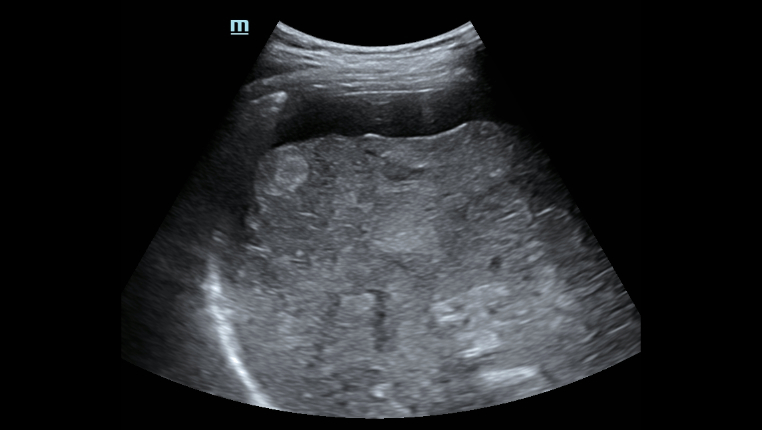

? ??? ?? ???? ???? ?? ???? Hepatus? ? ??? ??? ???? ??? ??? ?????. ???? ????? ??? ? ?? ??? ???? ????? ? ?? ???? ? ?? ??? ??? ??? ?????.

??? ???? ?? ? ??? ? ? ???? ?? ??, ??, ???? ? ?? ??? ??? ? ????. ?? ?? ???? ?????.

- ????? ??? ??

- ???? ? ??

- ?? B? ??

- ?? C? ??